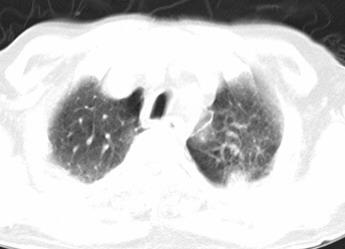

以下是引用xianxianzhongyi在2008-4-20 14:44:00的发言:[br]本人愚见:次病例短短两月的时间,呈现如此大面积实变,病变增长过于迅速,此其一。其二,病变在动脉早期既有明显强化。其三,左上叶后段及下叶背段多叶受累。其四,肺门及纵隔内未见明显肿大的淋巴结。估计层面较厚段支气管显示不清。 诊断:炎性实变可能性大。

以下是引用光影相伴在2008-4-20 14:39:00的发言:[br]支持:1)左侧中央型肺癌伴左肺上叶阻塞性肺炎。、[br] 2)双侧少量胸腔积液。